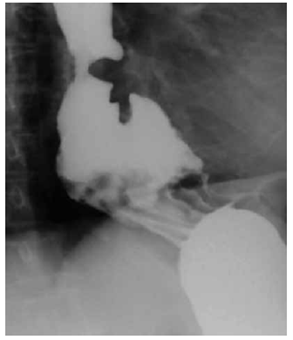

Mediante un esofagograma con bario, se observó dilatación leve del esófago medio y proximal, secundaria a la presencia de una hernia hiatal (figura 1). Inicialmente, se le dio tratamiento sintomático con un inhibidor de la bomba de protones y se le hizo seguimiento ambulatorio.